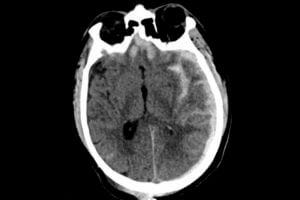

Fixing The Brain’s Plumbing After Head Injury May Prevent Alzheimer’s